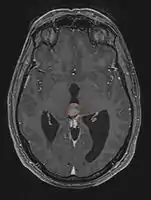

< Radiation Oncology < CNS

Pineal Gland Tumors

Clinical Presentation

• Determined by the spatial anatomy and direction of growth

• Obstruction of aquaduct: hydrocephalus presenting as headaches, nausea, vomiting

• Compromise of superior colliculus: vertical gaze palsy, pupillary and oculomotor nerve paresis (Parinaud syndrome)

• Progressive growth: cranial nerve neuropathies, hypothalamic dysfunction